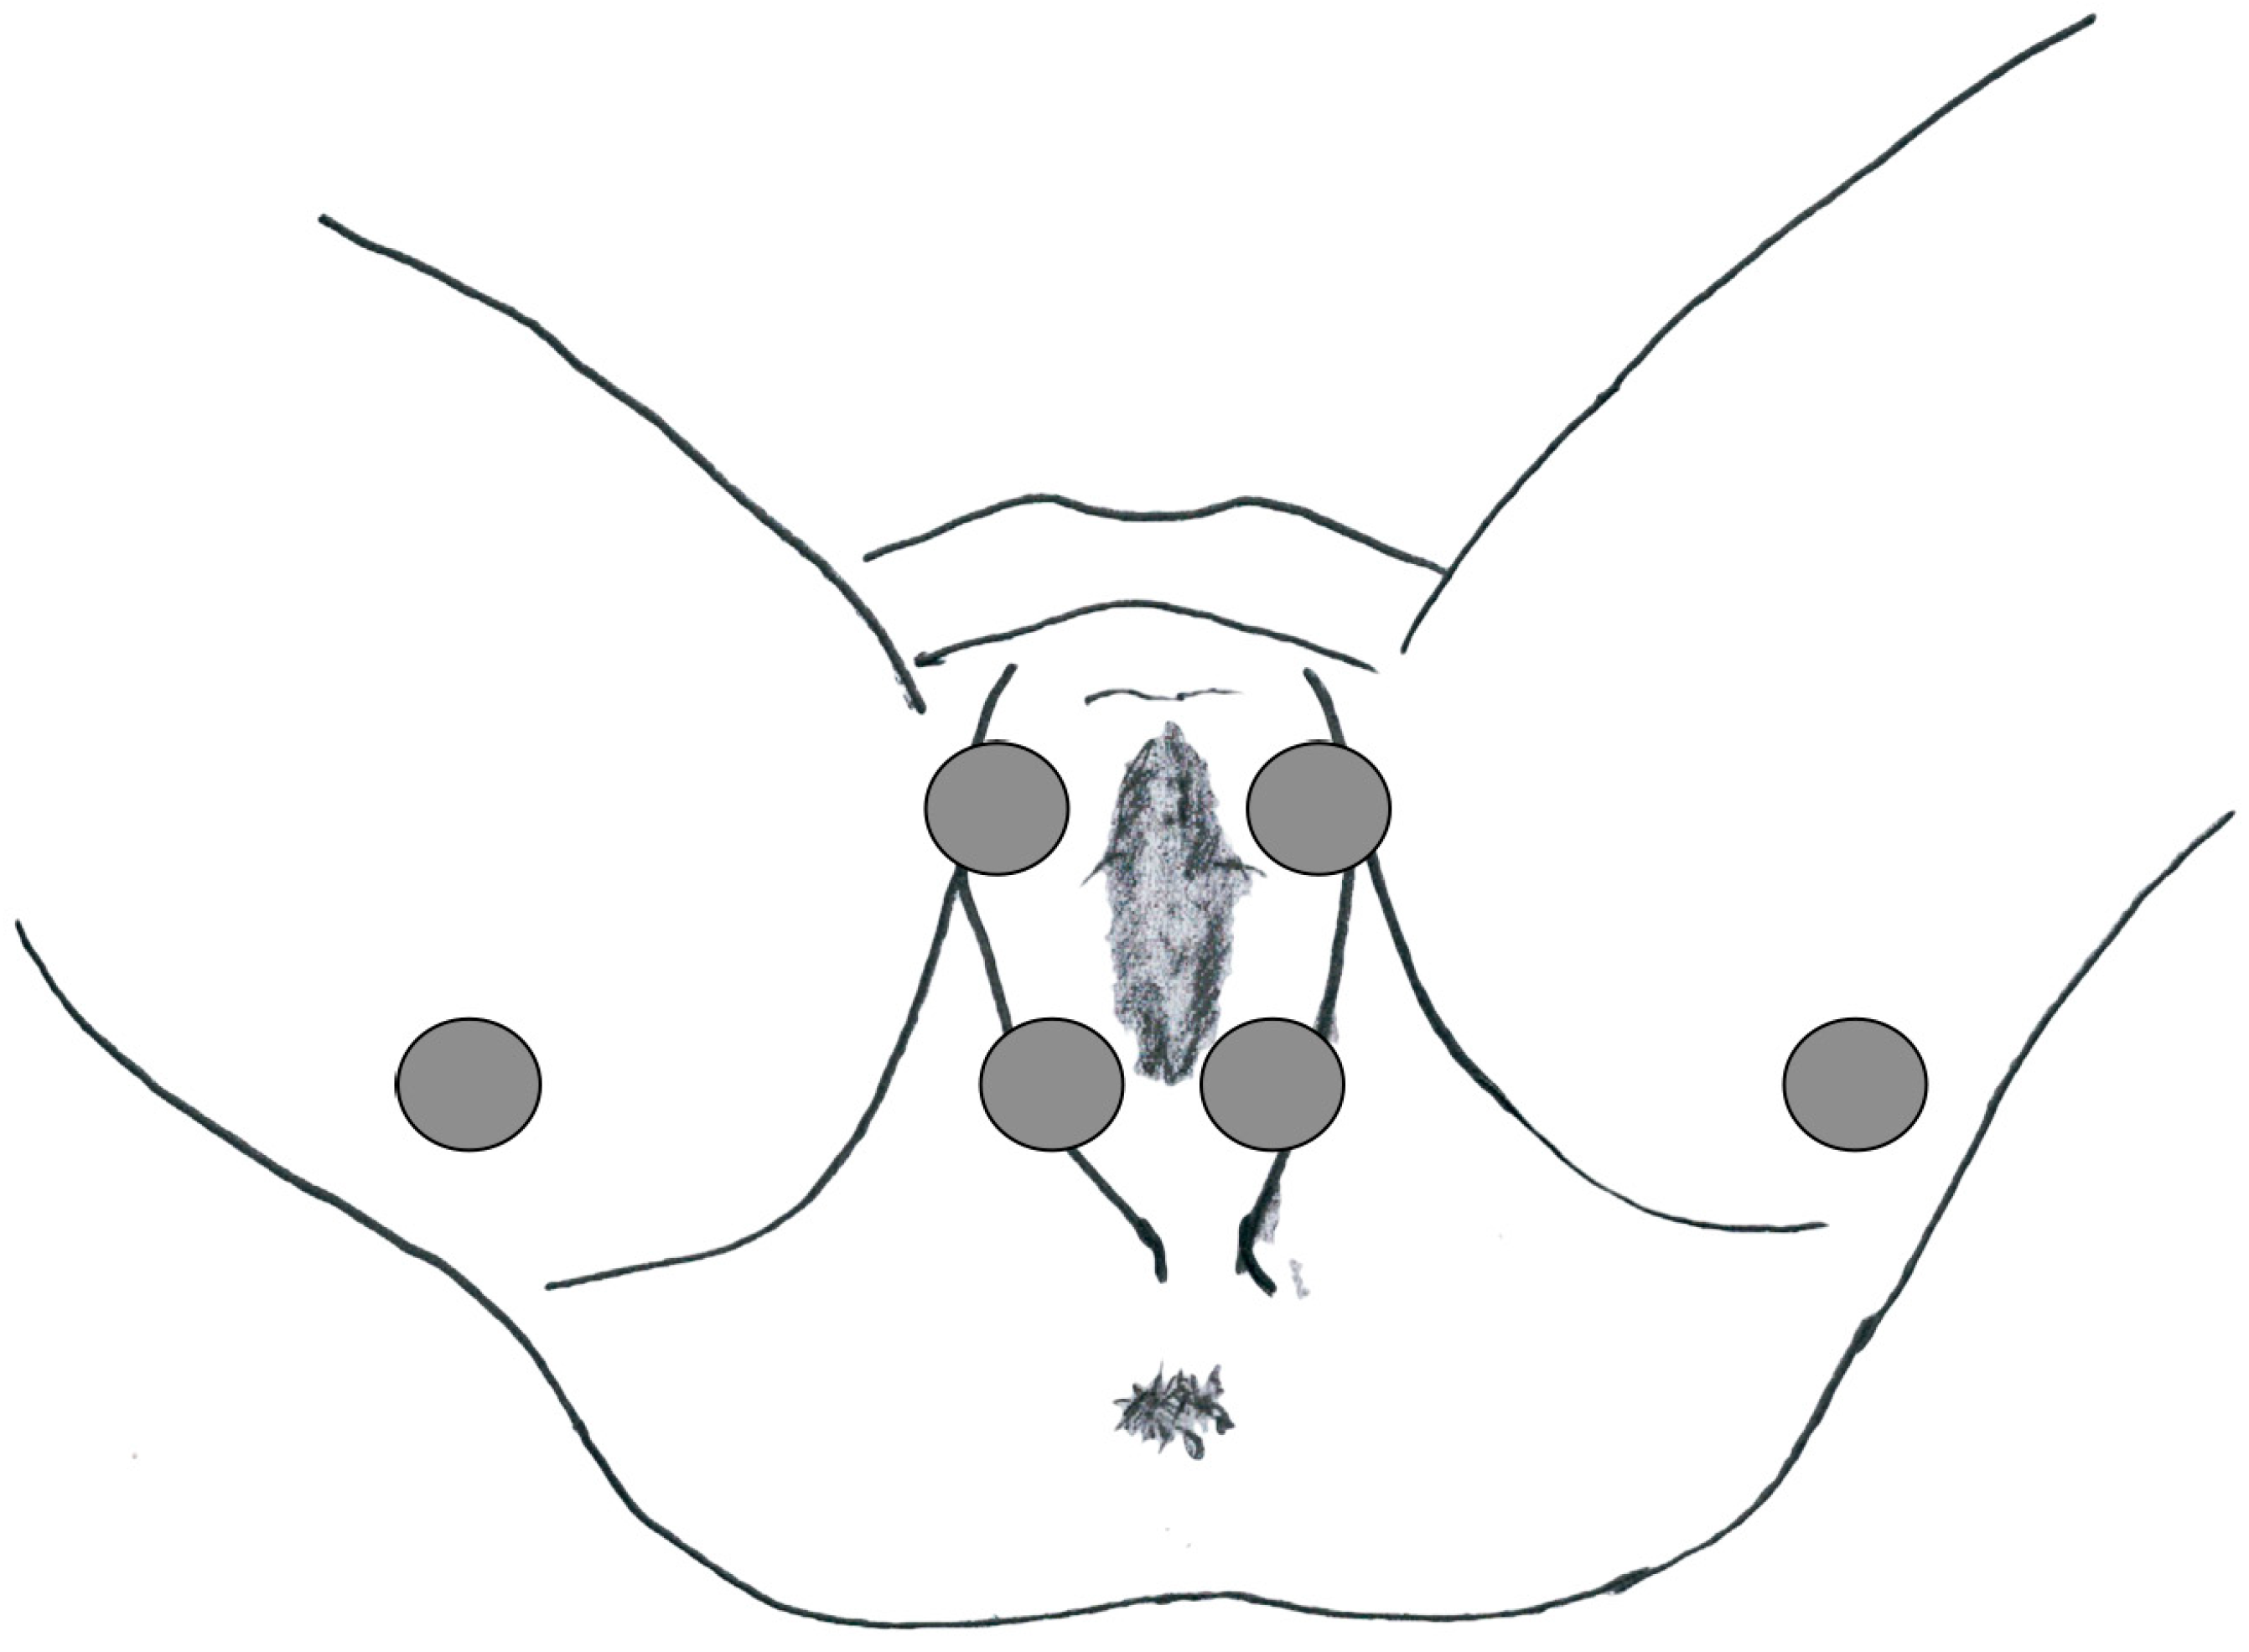

This study was approved by the local ethics committee and was conducted according to the principles of the Declaration of Helsinki. The human ethics review board at our institution approved the study design. Informed consent for data collection was obtained from all patients. To characterize PFM activity, a sEMG was carried out at baseline before endovascular treatment and 6 months after it. The latency of the P40 response (n.v. 37.68 ± 2.60 ms), the P1-N1 amplitude (n.v. 119 3.64 ± 1.01 μV) and the latency of the R1 early response (n.v. < 45 ms) were evaluated in the paraclitoral site (Figure 1).

Figure 1.

Electrode location for the PFM sEMG study.

sEMG signal Recording Technique. The sEMG signal was recorded in each patient from the left and right sides of the pelvic floor in a dorsal lithotomy position with adhesive electrodes. The study of the sacral evoked potentials was carried out with a manual bipolar stimulator with a cathode at the paraclitoral site and recorded using surface electrodes in the parietal region CZ (−2 cm)—FPZ according to the international 10–20 system, with square wave stimulation of the duration of 0.5 ms, intensity 3–4 times the sensory threshold, frequency 1.5 Hz, 151 impedance < 5 kOhm, bandwidth 1 Hz–3 kHz, 200 stimuli. The latency of the P40 response (n.v. 37.68 ± 2.60 ms) and the P1-N1 amplitude (n.v. 3.64 ± 1.01 μV) were evaluated. The anal pudendal reflex was evaluated with a manual bipolar stimulator with the cathode positioned in the paraclitoral site and recorded by means of coaxial needle electrodes from the external anal sphincter muscle. The latency of the R1 early response was evaluated (n.v. < 45 ms).